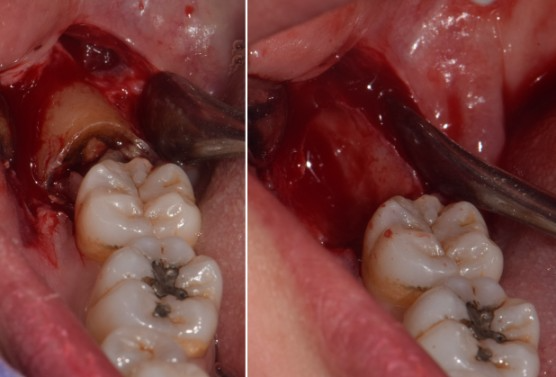

사랑니#48 사랑니 발치

치료 기간  2024. 03. 12 당일 치료

cc. #48 발치 원하심

K01.173 하악 제3대구치 의 매복